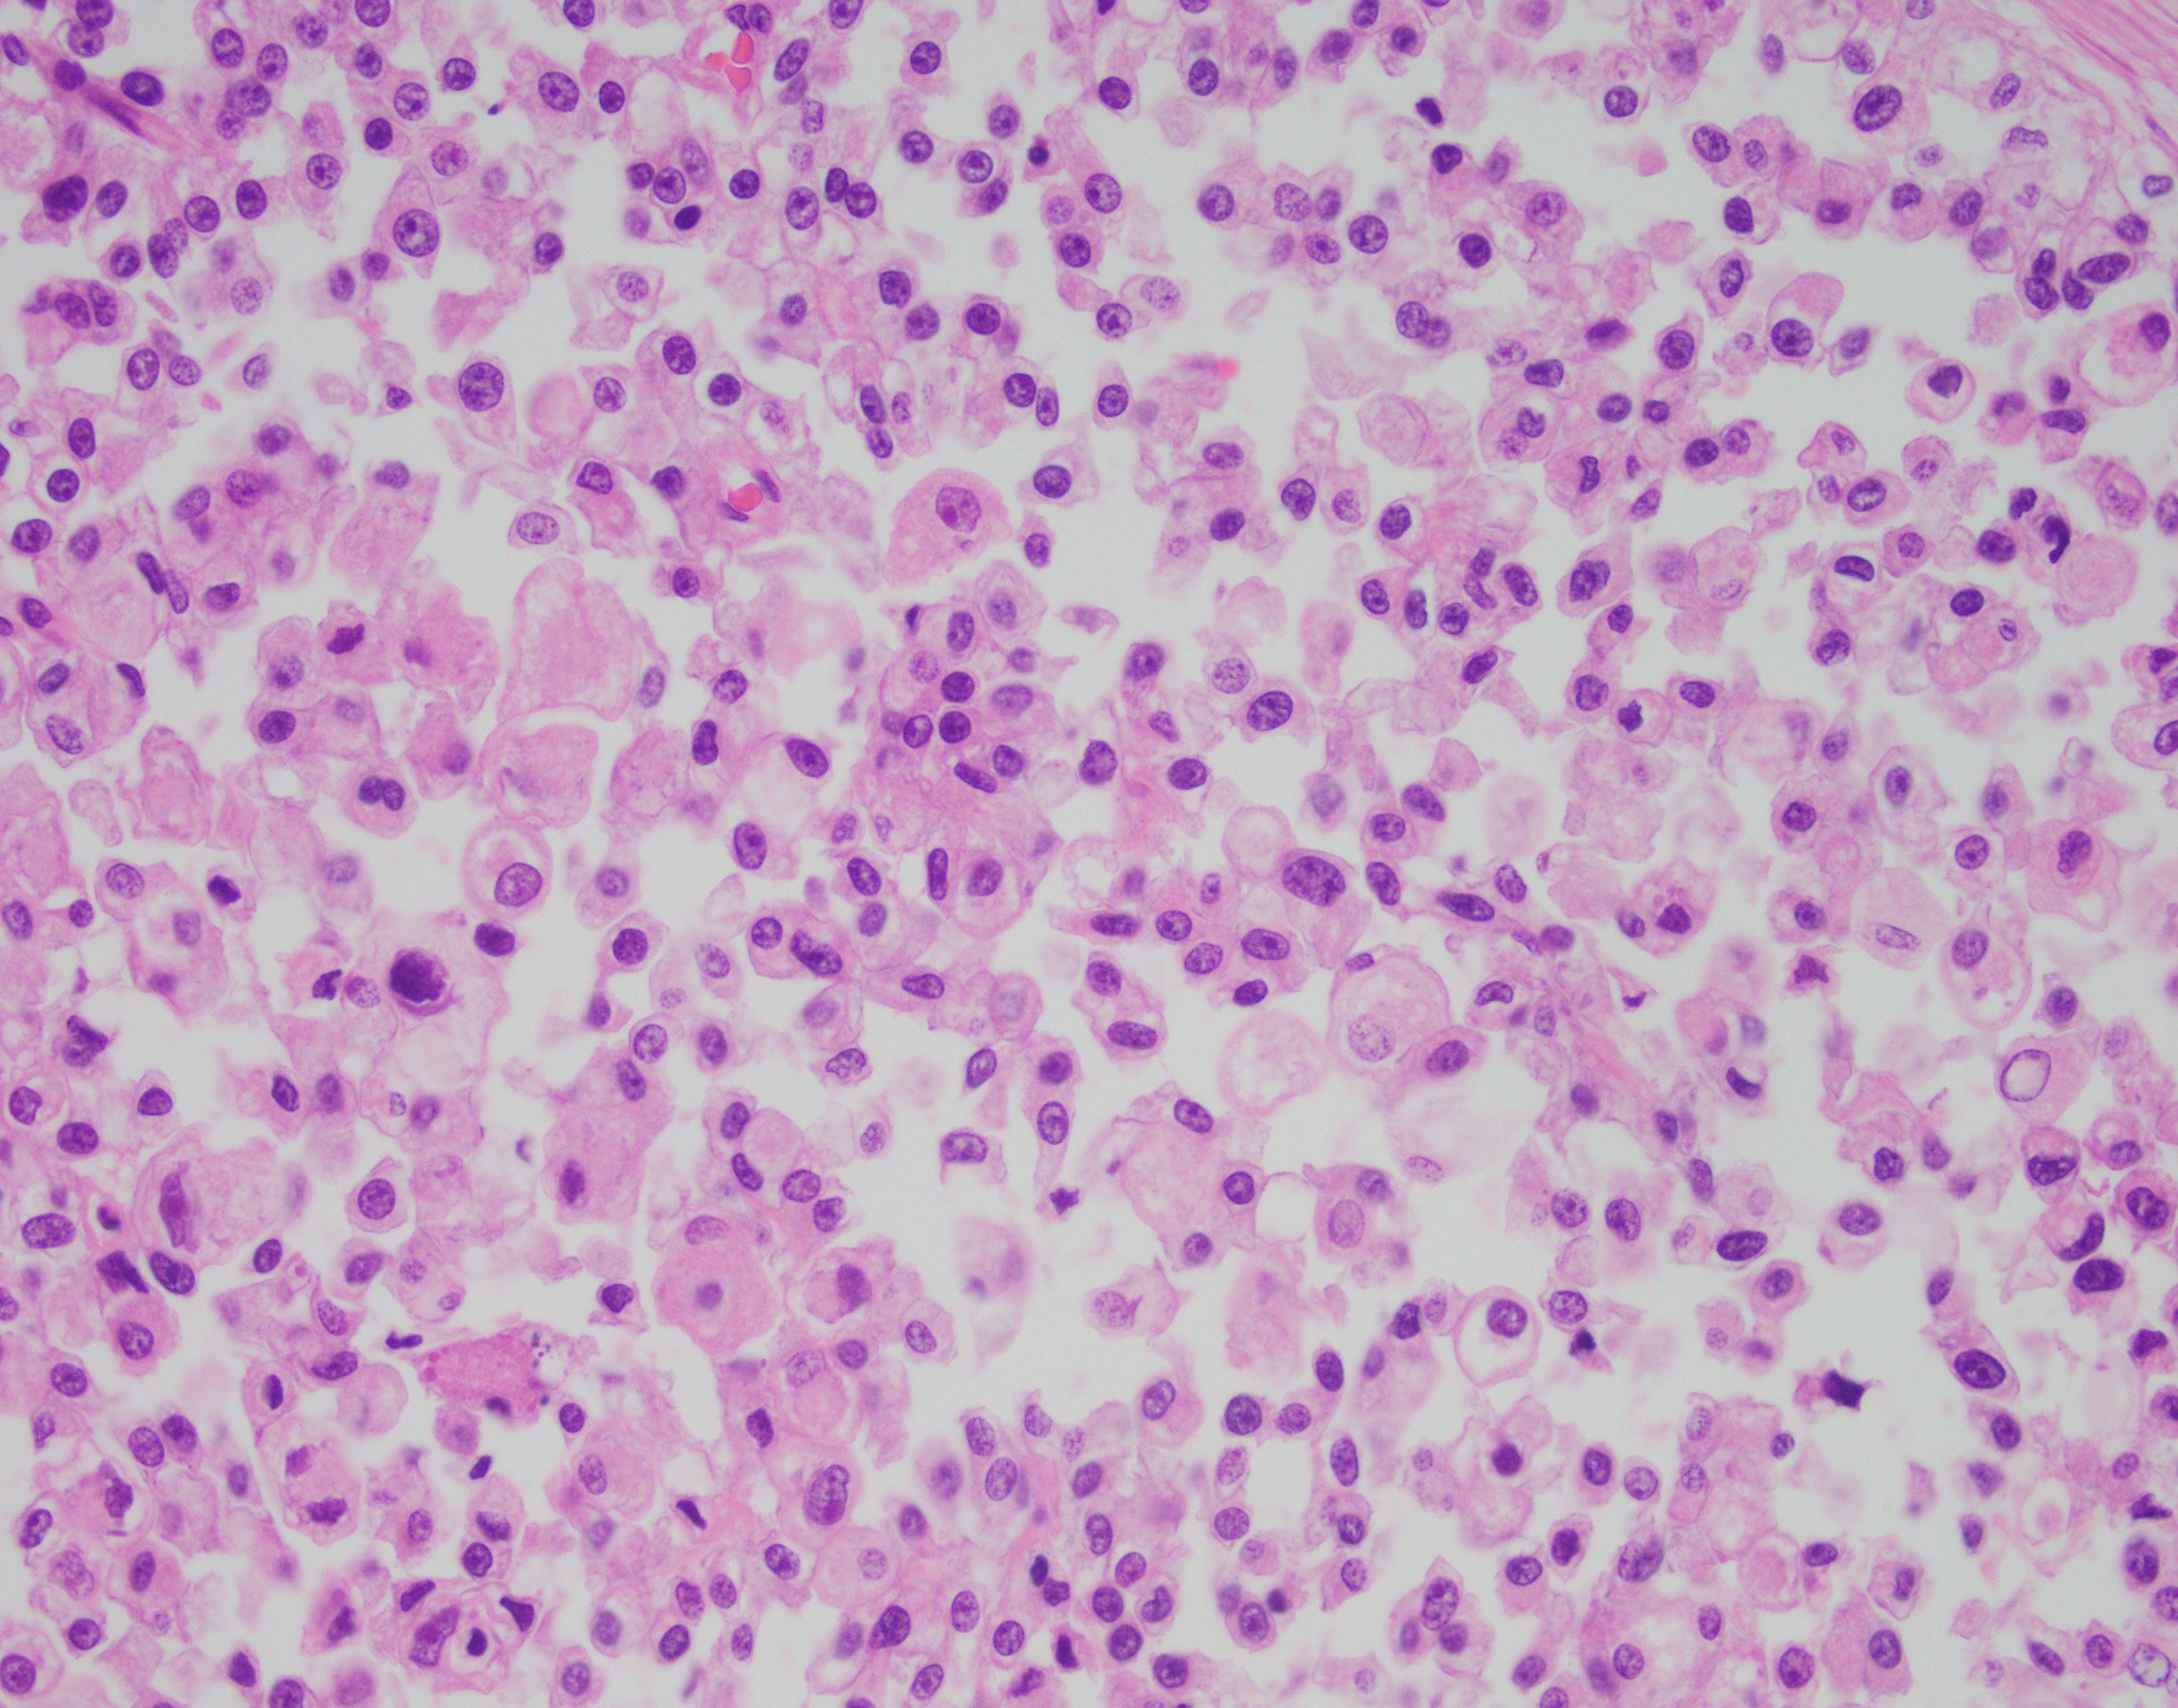

The findings in this case show a diffuse, infiltrative, and discohesive tumor extending into the perivesical adipose tissue. There is extensive perineural and lymphovascular invasion. Focal areas show urothelial carcinoma in situ. Tumor cells have eosinophilic cytoplasm, and nuclei are eccentrically located with focal signet ring cell features. Staining with p63 and GATA3 was performed and shows positivity in both stains.

These features are all consistent with the plasmacytoid variant of urothelial carcinoma. Typically, this variant grows in a linitis plastica-like manner. Tumor infiltration is diffuse, in single cells or cords. Characteristically, tumor cells exhibit eccentric nuclei and/or signet ring cell morphology. Of note, these tumors stain similar to usual urothelial carcinomas, but also strongly express CD138 and lose E-cadherin expression. Most tumors are locally advanced at the time of diagnosis and are highly aggressive.